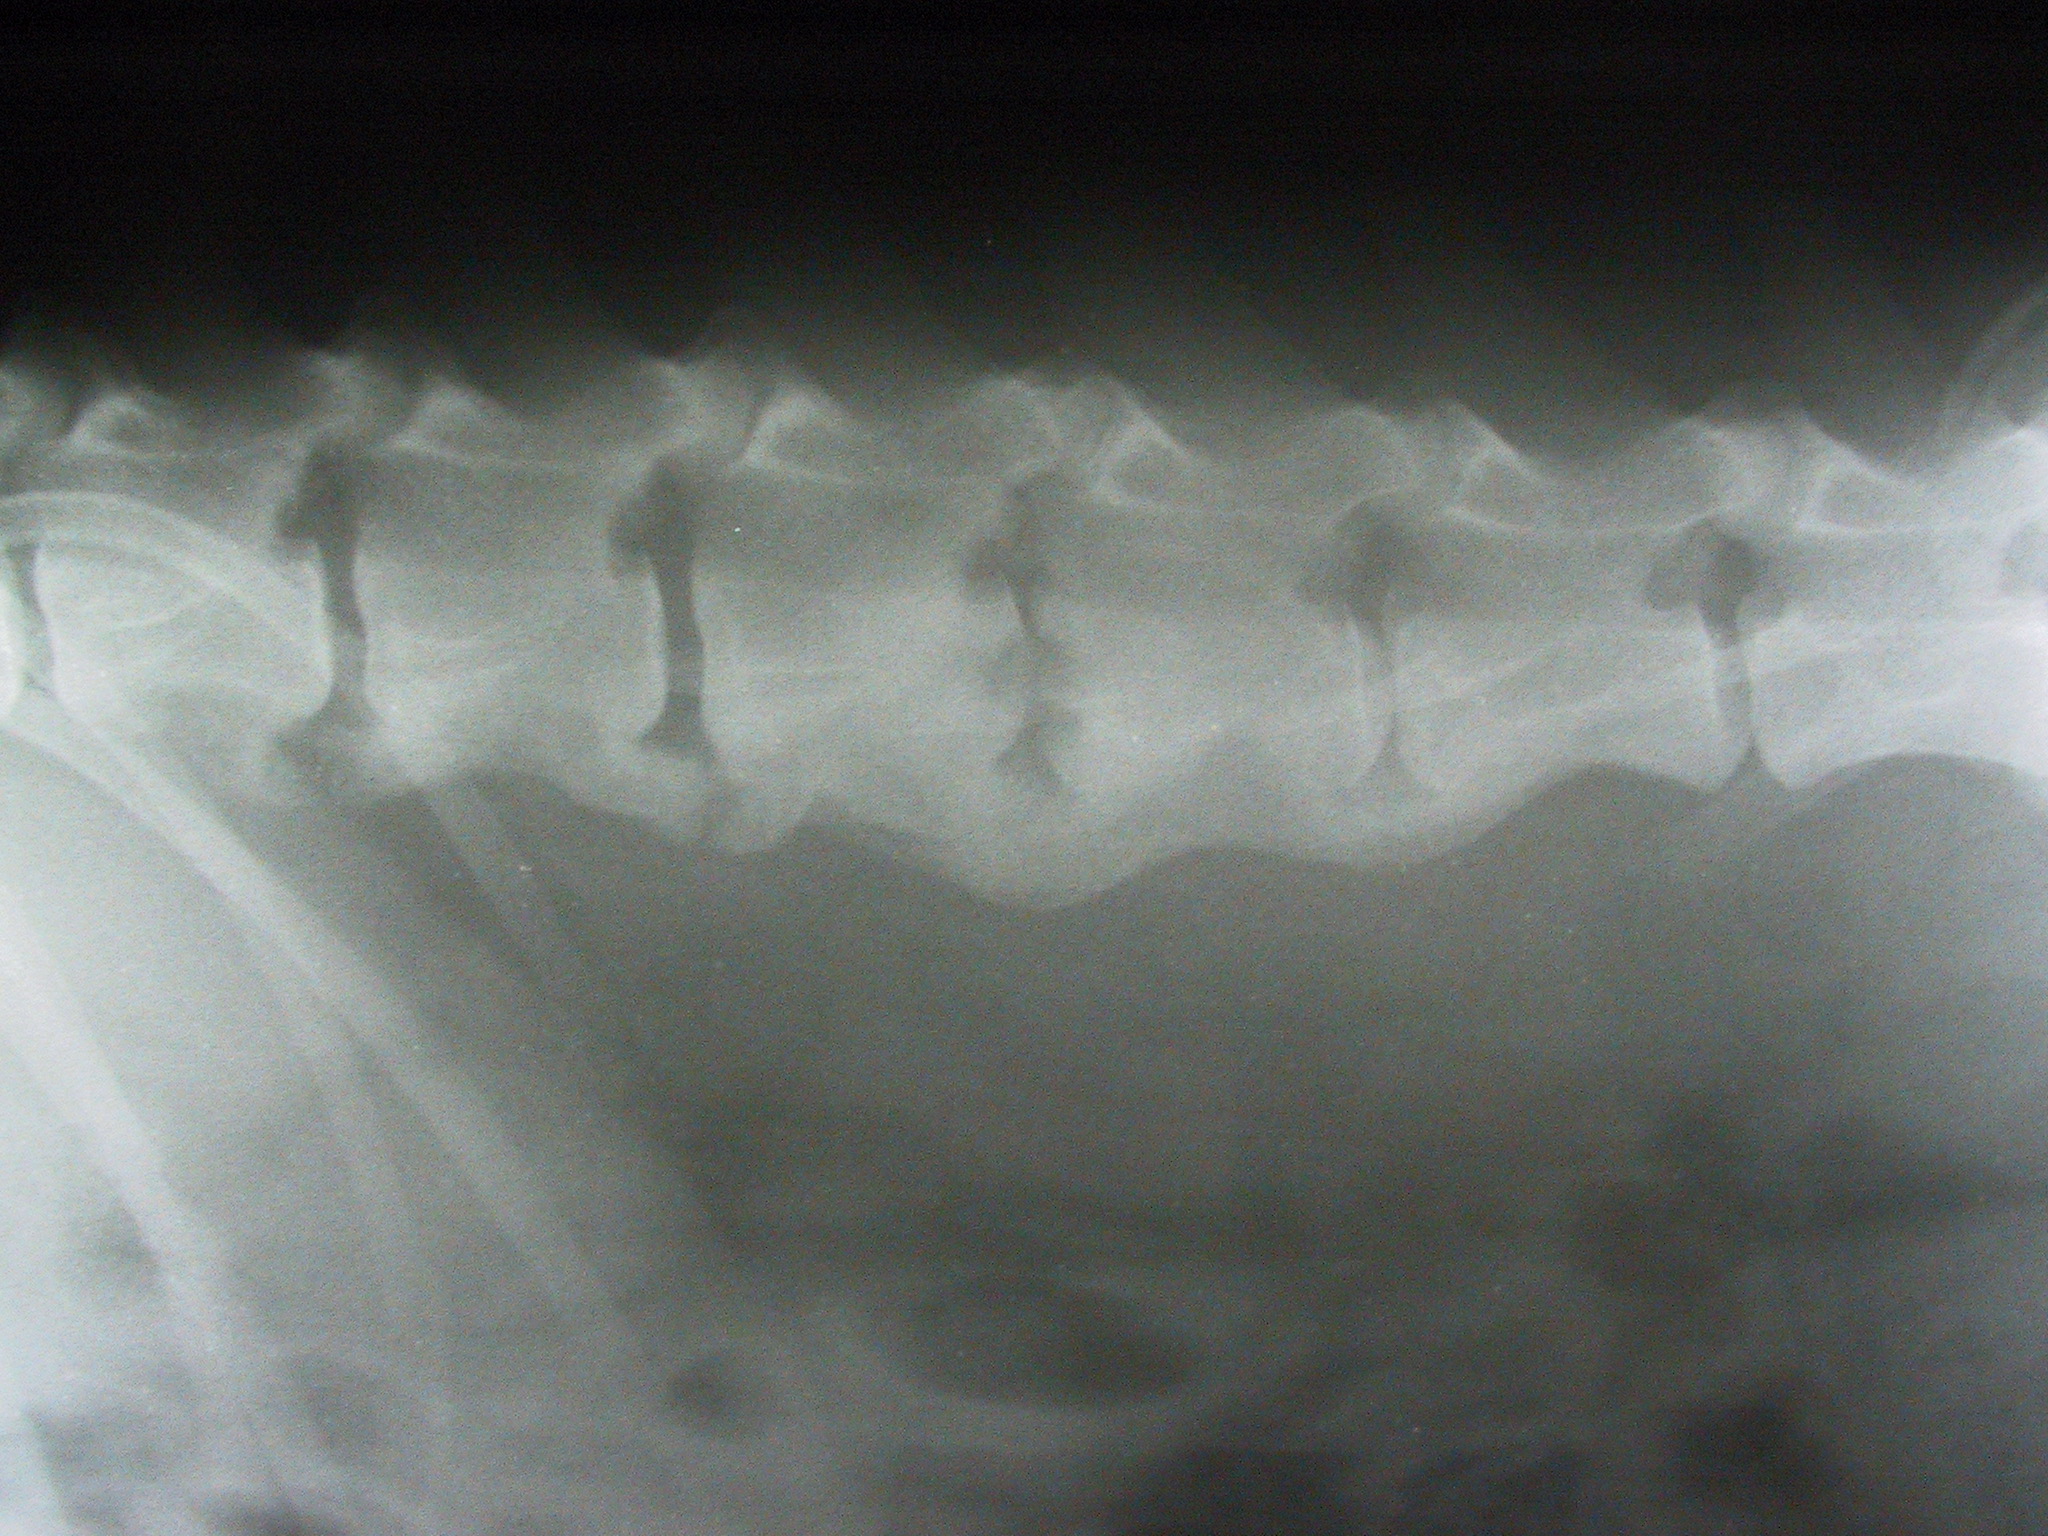

Spondyloarthrosen, Diskospondylitis